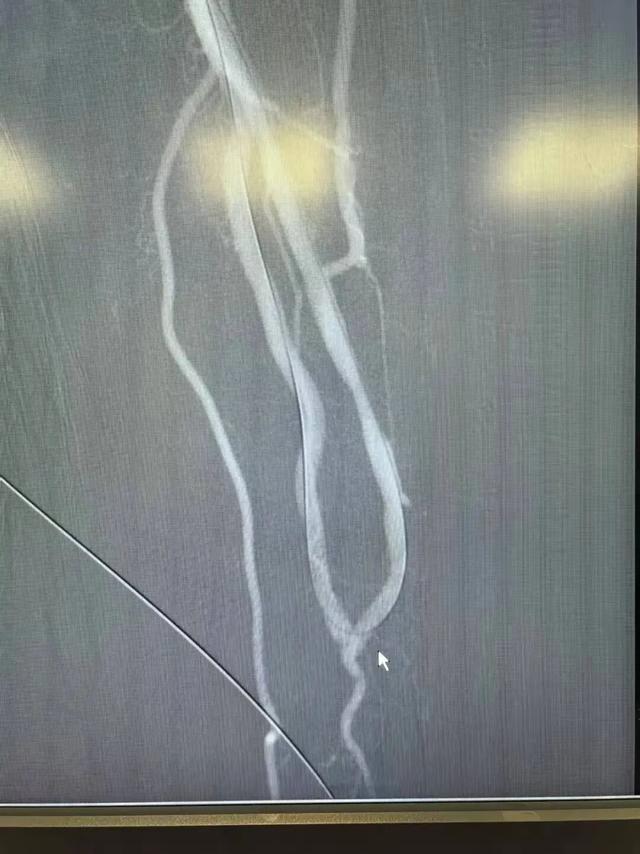

▲左前臂内瘘血管吻合口闭塞

▲术中球囊扩张、开通闭塞血管

▲左前臂内瘘闭塞血管已成功开通、血流通畅

手术室内,DSA(数字减影血管造影)设备像一双“透视眼”,清晰显示出血管闭塞的位置和程度。医生将一根极细的导丝,小心翼翼地穿越堵塞段,随后沿导丝送入球囊——轻轻加压,逐级球囊扩张,被堵死的血管壁被缓缓撑开。血流重新奔涌。整个手术仅留下一个穿刺针眼。术后复查显示,闭塞血管恢复通畅,内瘘震颤及血管杂音即刻重现。